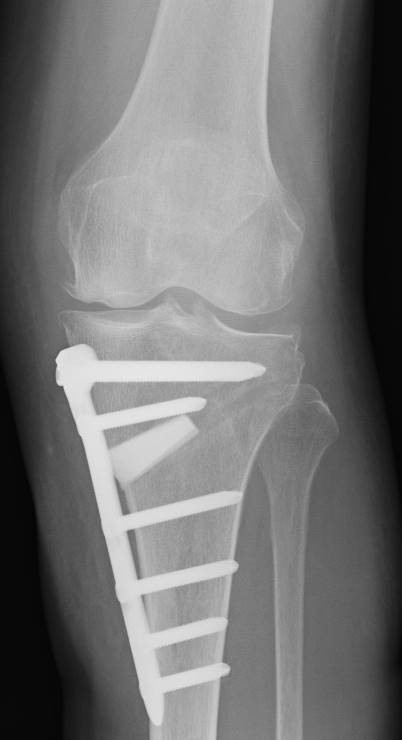

すね(脛骨)の内側を骨切りして、骨切り部分を開いていく方法です。術後の骨切り部安定性は良いので、早くから屈曲訓練や歩行訓練が可能です。

1週間の装具固定を行います。部分的に体重をかける歩行訓練は術後1週間から開始します。術後2週間たってから全部の体重をかけて歩く練習を始めます。退院は歩行が安定して、屈曲角度が120度まで得られると可能です。

問題点は?

1.すね(脛骨)の内側に傷ができますが、この部分は皮下脂肪が少ないために術後に内固定材料(骨を固定するプレート)による痛みが出ることがあります。術後6~12か月で骨がくっつけばプレートを抜去することが可能です。

2.足の長さが少し長くなります。O脚を真っすぐにするだけで足は長くなるのですが、この手術の場合、さらに骨切り部分を開くためにすね(脛骨)の骨が長くなります。多くの場合、リハビリ訓練で骨盤や背骨の傾きを変化させることで、両足の長さの違いは矯正することができます。